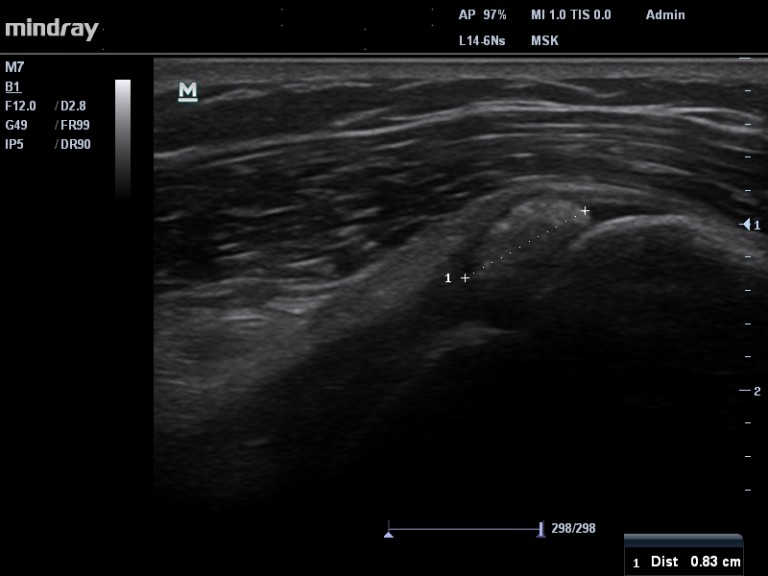

LA PHASE FORMATIVE, est certainement la phase où nous recevons le plus de patients en consultation. Très clairement : plus la calcification est volumineuse (> 1cm) et plus elle déforme le tendon ( Images 1 et 2) donc plus le risque d’avoir une épaule douloureuse est important.  Les douleurs peuvent durer des mois , voire des années, si le patient non traité,  n’a pas la « chance » d’avoir une résorption spontanée. Il existe toute une série de traitements possibles lors cette phase :

Image 1. Calcification de type 2, dont une partie déforme le tendon (flèche rouge)